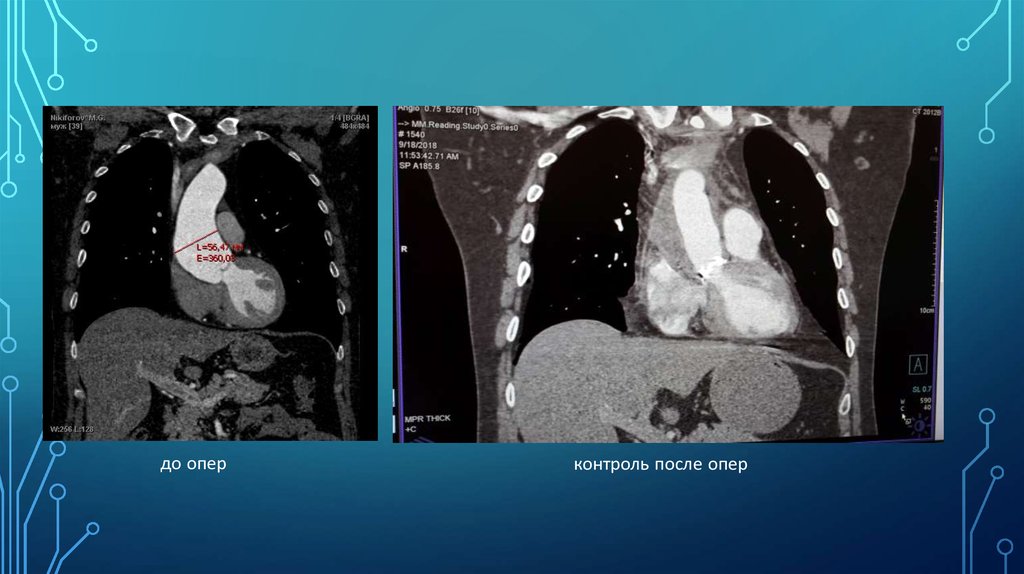

• пациент 40 лет

• длительный анамнез ГБ

• с детства знает о двустворчатом АоК

• в начале 2018 при КТ-ангиографии диагностирована аневризма восх.

аорты (макс. размер 60 мм)

до опер

контроль после опер